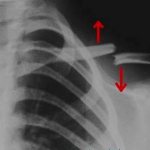

• рентгенография;